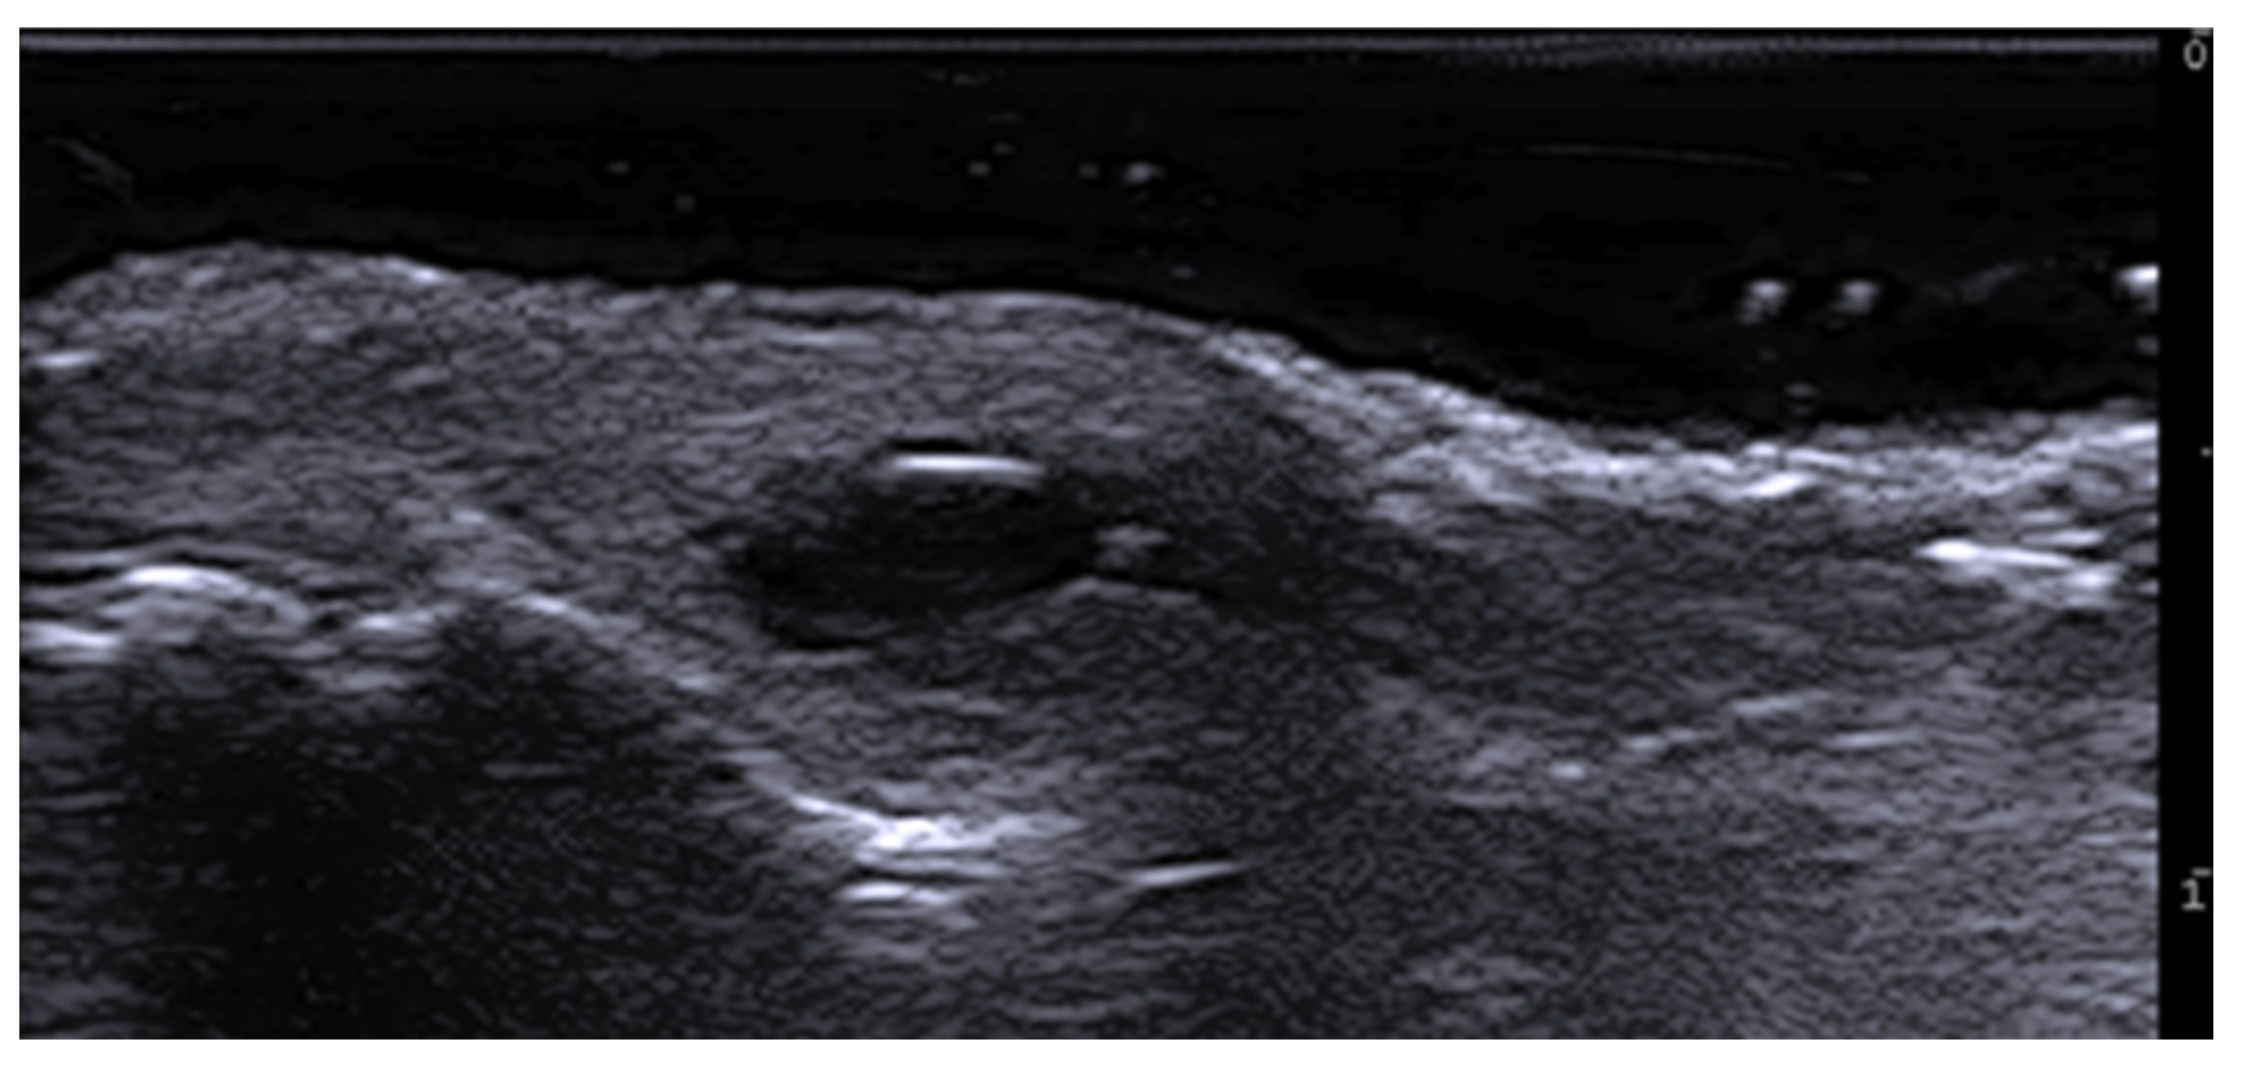

- Cataldo-Cerda, K.; Wortsman, X. Dissecting Cellulitis of the Scalp Early Diagnosed by Color Doppler Ultrasound. Int. J. Trichology 2017, 9, 147–148. [Google Scholar] [CrossRef]